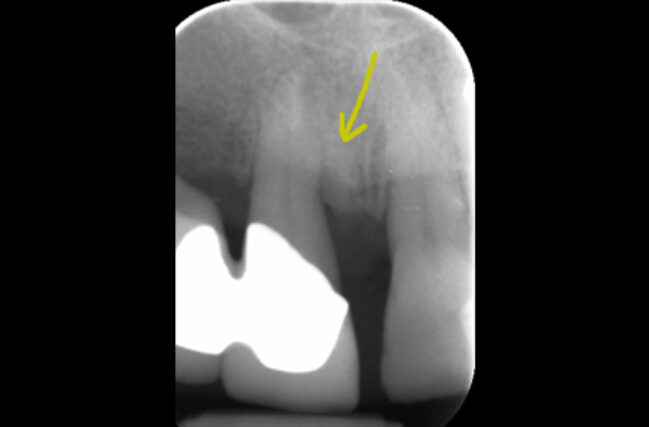

Periodontitis is the more severe form of gum disease, this is irreversible. Periodontitis involves the loss of supporting bone, as a result, in addition to the symptoms of gingivitis, it can also cause receding gums, gaps in between teeth, bad breath and wobbly teeth.